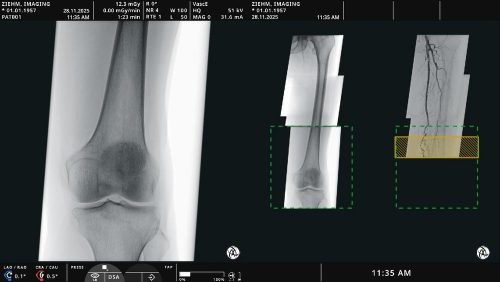

Stereotaxie-Systeme ermöglichen eine hochpräzise Führung von minimal-invasiven Instrumenten in das menschliche Gehirn. Die komplexen Systeme bedingen höchste Anforderungen und werden nur in kleinen Stückzahlen für hochspezialisierte Eingriffe benötigt, weshalb die Entwicklung und Herstellung derzeit mit hohen Kosten und Aufwand verbunden sind.

Die Fertigung nach aktuellem Stand der Technik bringt einige Nachteile mit sich: begrenzte Möglichkeiten in der Neu- oder Weiterentwicklung von Produkten, stark verlängerte Entwicklungszyklen und Einbußen auf Grund von werkstoff- und prozessseitigen Einflussfaktoren. Beispielsweise hat die Fertigung aus metallischen Werkstoffen einen negativen Einfluss auf Gewicht und die Eignung für MRT- oder CT-Bildgebung (unerwünschte Artefakte in der Bildgebung). Auch zukünftige Anforderungen personalisierter Medizinprodukte, können nur schlecht mit konventionellen Fertigungsverfahren realisiert werden.